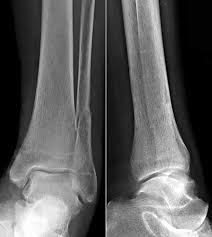

KLASIFIKASI FRAKTUR WEBER Drsimon ponco septiono f Weber A Garis fraktur berada dibawah syndemiosis thibiofibularis f Weber B Garis fraktur berada setinggi syndemiosis thibiofibularis f Weber C Garis fraktur berada diatas syndemiosis thibiofibularis f. Weber C Fraktur immer Weber A- und Weber B- Frakturen mit. Many translated example sentences containing Weber c Fraktur English-German dictionary and search engine for English translations.

Weber C Fraktur. Neben der Weber C Fraktur gibt es auch noch die Fraktur der Klasse A und B. Was ist eine Weber-C-Fraktur. DayZ sa well kit DayZ Expansion Building Kits - YouTub. Verschobenem Bruch dislozierte Fraktur undoder. It has a role in determining treatment. Weber C Fraktur. Look up the French to German translation of weber c fraktur in the PONS online dictionary. The Weber ankle fracture classification or Danis-Weber classification is a simple system for classification of lateral malleolar fractures relating to the level of the fracture in relation to the ankle joint specifically the distal tibiofibular syndesmosis.